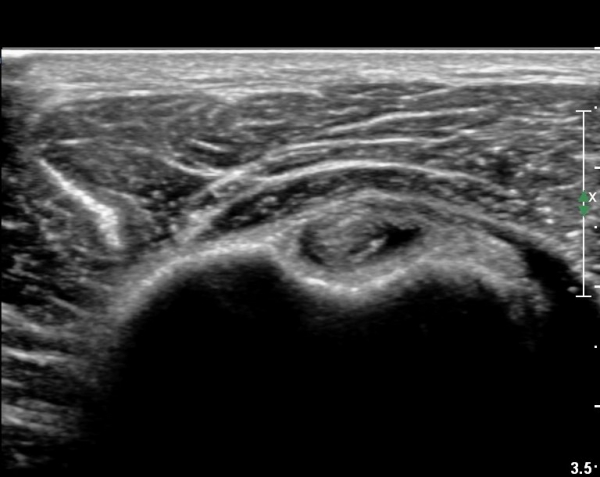

°ß°©ÇÏ±Ù°Ç »óºÎ Á¾´Ü¸é°Ë»ç¿¡¼­ °ß°©ÇϱٰǠ ÆÄ¿­ÀÌ ¶Ñ·ÈÇÔ(»çÁø 4, 5).